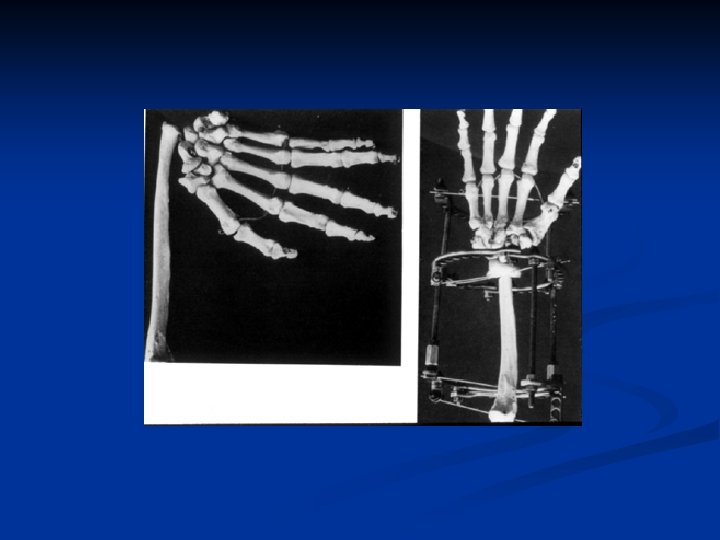

8 year followup

7 yr. followup radiographs